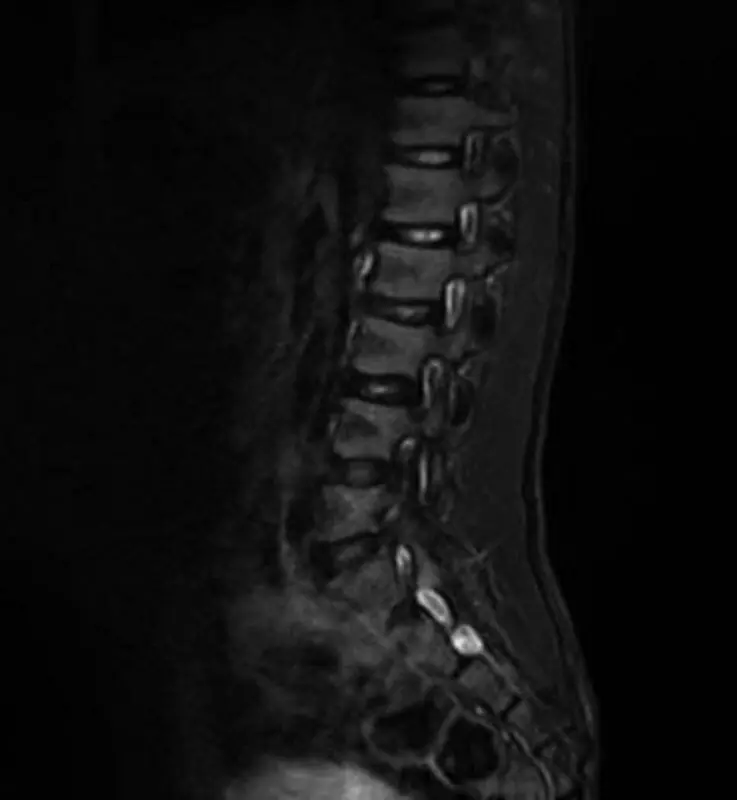

肌肉呈低紧张性,皮下组织不良。患者表现为踝关节瓣膜狭窄,膝关节挛缩,龙骨胸,肩胛翼,腕关节松弛和腹直肌痉挛。 发育迟缓,言语非常重。步态不稳定。髌骨骨性坏死反射消失不合格。收缩期小鼠2/6Levine突出,超声心动图证实存在心房间隔缺损并伴有肺动脉瓣狭窄。常规实验室分析电解质、血浆和尿液氨基酸、甲状腺标志物、有机酸、血浆嘌呤和转铁蛋白等电点电力电泳显示有左侧停留睾丸,总胆固醇在正常范围内。清醒和睡眠时的脑电图是正常的。用扩散强调成像序列的脑磁共振成像法(MRI)显示,脑膜下和脑膜上结构和脑室的体积和解剖结构都很规则。脊柱MRI检查发现,S5后弓部有裂隙,S3至S5的骶骨远端有脂肪肿症,右侧S2有一个Tarlov型的小包膜囊肿(见图1、2)。

图2 旋磁共振成像显示S2心尖部周围囊肿。